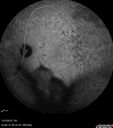

SPECTRALIS-SD-OCT SCAN: The OCT scan through the macula in the right eye shows the mass to be intraretinal and in the left eye there are irregularities at the level of the pigment epithelium.